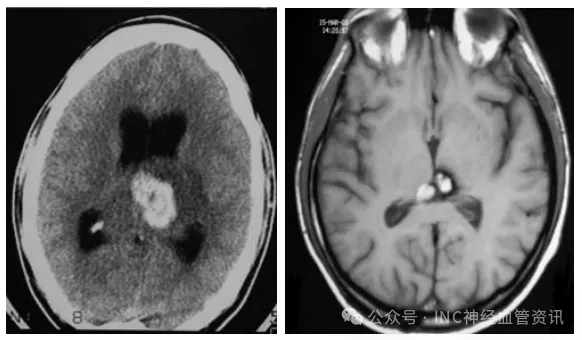

头颅CT检查显示其丘脑区域存在出血性病灶,初诊医生判断为"丘脑肿瘤",遂决定进行放射治疗。

图1,左图:头颅CT扫描显示初诊为丘脑肿瘤的病变;右图:接受40Gy分割放疗一年后,磁共振成像将左丘脑病变重新评估为丘脑海绵状血管瘤。与未照射的对照海绵状血管瘤组织样本比较,可见治疗后病变间质存在内皮细胞破坏和显著纤维化表现。

尽管预期放疗能消除病灶,但一年后患者症状复发。新的磁共振检查结果推翻了初始诊断:该病灶实为丘脑海绵状血管瘤!更为复杂的是,放疗不仅未解决问题,反而出现病灶持续出血的情况。